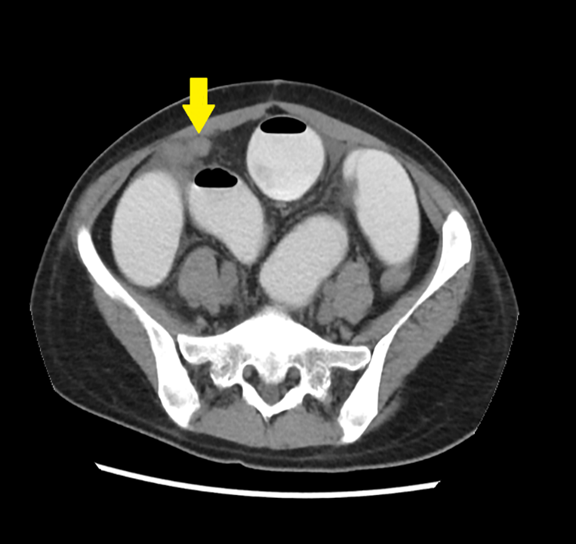

Multidetector computed tomography (MDCT) of the abdomen with oral non-ionic contrast demonstrated a tubular structure arising from the distal ileum, showing two adjacent transition points (the “double-beak” sign), a C-shaped closed-loop configuration, and convergence of mesenteric vessels toward the diverticular base. These findings were consistent with a closed-loop small bowel obstruction (SBO) secondary to Meckel’s diverticulum. [Figure 2] [Figure 3] [Figure 4]

Figure 2: Axial contrast-enhanced CT image of the lower abdomen shows dilated loops of contrast-filled small bowel, consistent with small bowel obstruction. A blind-ending tubular structure tethered toward the terminal ileum (yellow arrow) is visualized, representing a Meckel’s diverticulum, which appears to be the lead point causing obstruction.